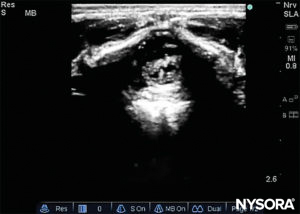

The probe is positioned first in a transverse plane at the sacrum level; this is called the short-axis view (SAX). The exact position of the cornua and the sacrococcygeal membrane (SCM) are defined (Figure 4). With the sacrococcygeal membrane in the middle of the image (Figure 5), the probe is then rotated 90 degrees into a midline sagittal position over the lower sacrum, which is called the long-axis view (LAX; Figure 6). The SCM and the ventral and dorsal layer of the os sacrum, with the caudal epidural space in between, are easily identified. In small children, the dural sac may be visible in this position, although in older children you need to scan more in a more cephalad direction (Figure 7). These movements can be performed in the opposite order, but a complete exploration of the space in both axes is recommended.

FIGURE 5. US image in the short-axis view showing the sacral cornea and sacrococcygeal membrane.